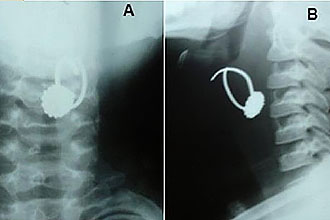

Наиболее часто встречающейся причиной, при которой начинает колоть в горле, является травма или присутствие постороннего предмета. Травмировать горло можно при употреблении крупных кусков твердой пищи, при случайном проглатывании костей из рыбы и мяса, различными твердыми предметами.

Часто именно дети травмируют горло, пытаясь проглотить твердые или острые предметы.

Поэтому, если после употребления в пищу, например, рыбы, резко возникает сильная боль в горле, то данный симптом будет типичным признаком нарушения поверхности слизистой глотки. Если имеет место травма, то болевые ощущения и чувство присутствия постороннего предмета будут усиливаться при глотании.

Первой помощью при возникновении травмы горла будет удаление инородного предмета и незамедлительное обращение к врачу во избежание осложнений.

Опасность подобного рода травм заключается в том, что через время болевые ощущения могут утихнуть, создавая иллюзию выздоровления, тогда как раздражитель останется в горле. Единственное, что испытывает больной в такой ситуации – небольшое покалывание. Однако часто в месте

локализации травмы, будь то порез или прокол, может остаться инородный предмет, например, осколок косточки, которая всего через несколько дней станет причиной развития воспалительного процесса. Абсцесс возникает вокруг инородного предмета, становясь причиной недомогания, которое сопровождается повышением температуры тела, ухудшением общего самочувствия, головными болями, интенсивной болью в горле. Если травма горла привела к возникновению нагноения, то в данном случае чаще всего не обойтись без хирургического вмешательства и активной антибиотикотерапии.